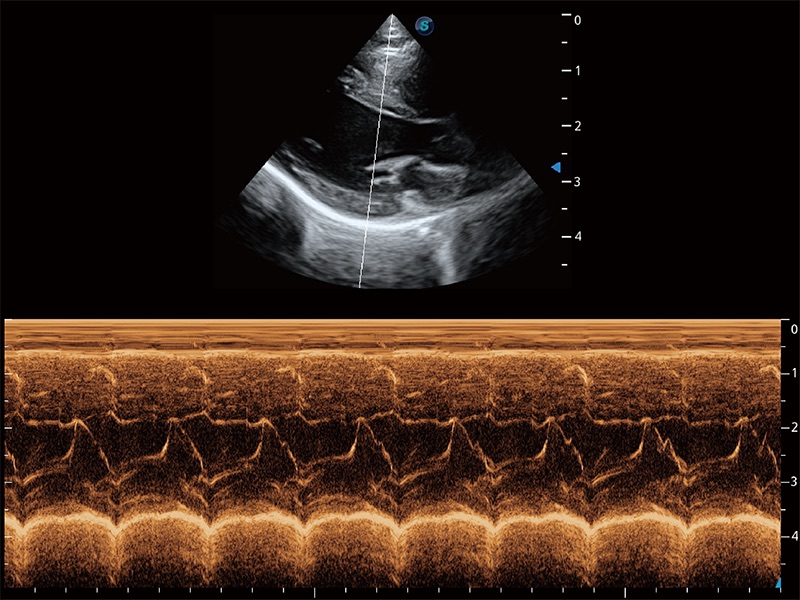

ProPet 80 配備了豐富的心臟探頭群、先進(jìn)的成像技術(shù)和專業(yè)的心臟測(cè)量工具,可幫助動(dòng)物醫(yī)生為不同體型和生理結(jié)構(gòu)的動(dòng)物提供心臟和心肌功能的全面評(píng)估。

通過(guò)360度任意調(diào)節(jié)3條M型取樣線,在同一心動(dòng)周期上觀察心臟不同位置的運(yùn)動(dòng)曲線,得到準(zhǔn)確的心功能測(cè)量數(shù)據(jù),有效評(píng)估心肌運(yùn)動(dòng)及左心室功能。